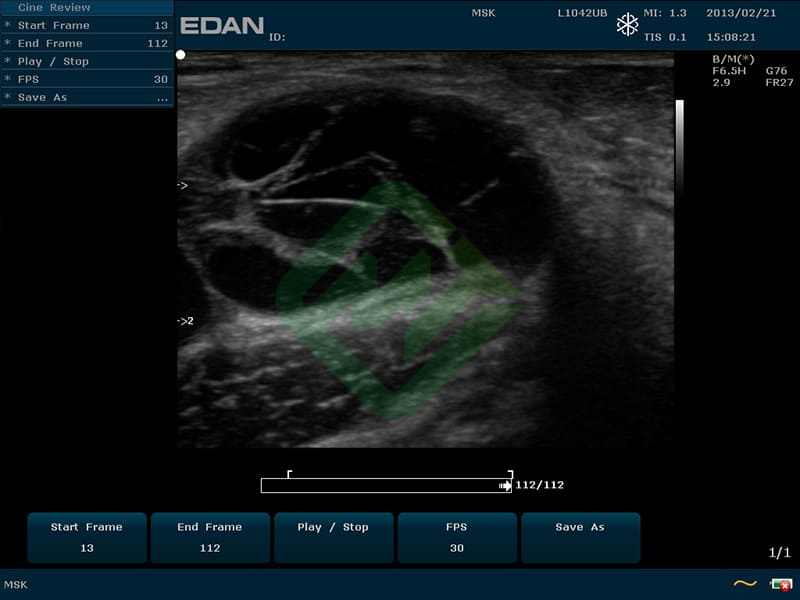

— линейным L742UB: частотный диапазон датчика 5–10 МГц, апертура 40 мм, глубина сканирования 130 мм, количество элементов 128

— линейный датчик Edan L1042UB